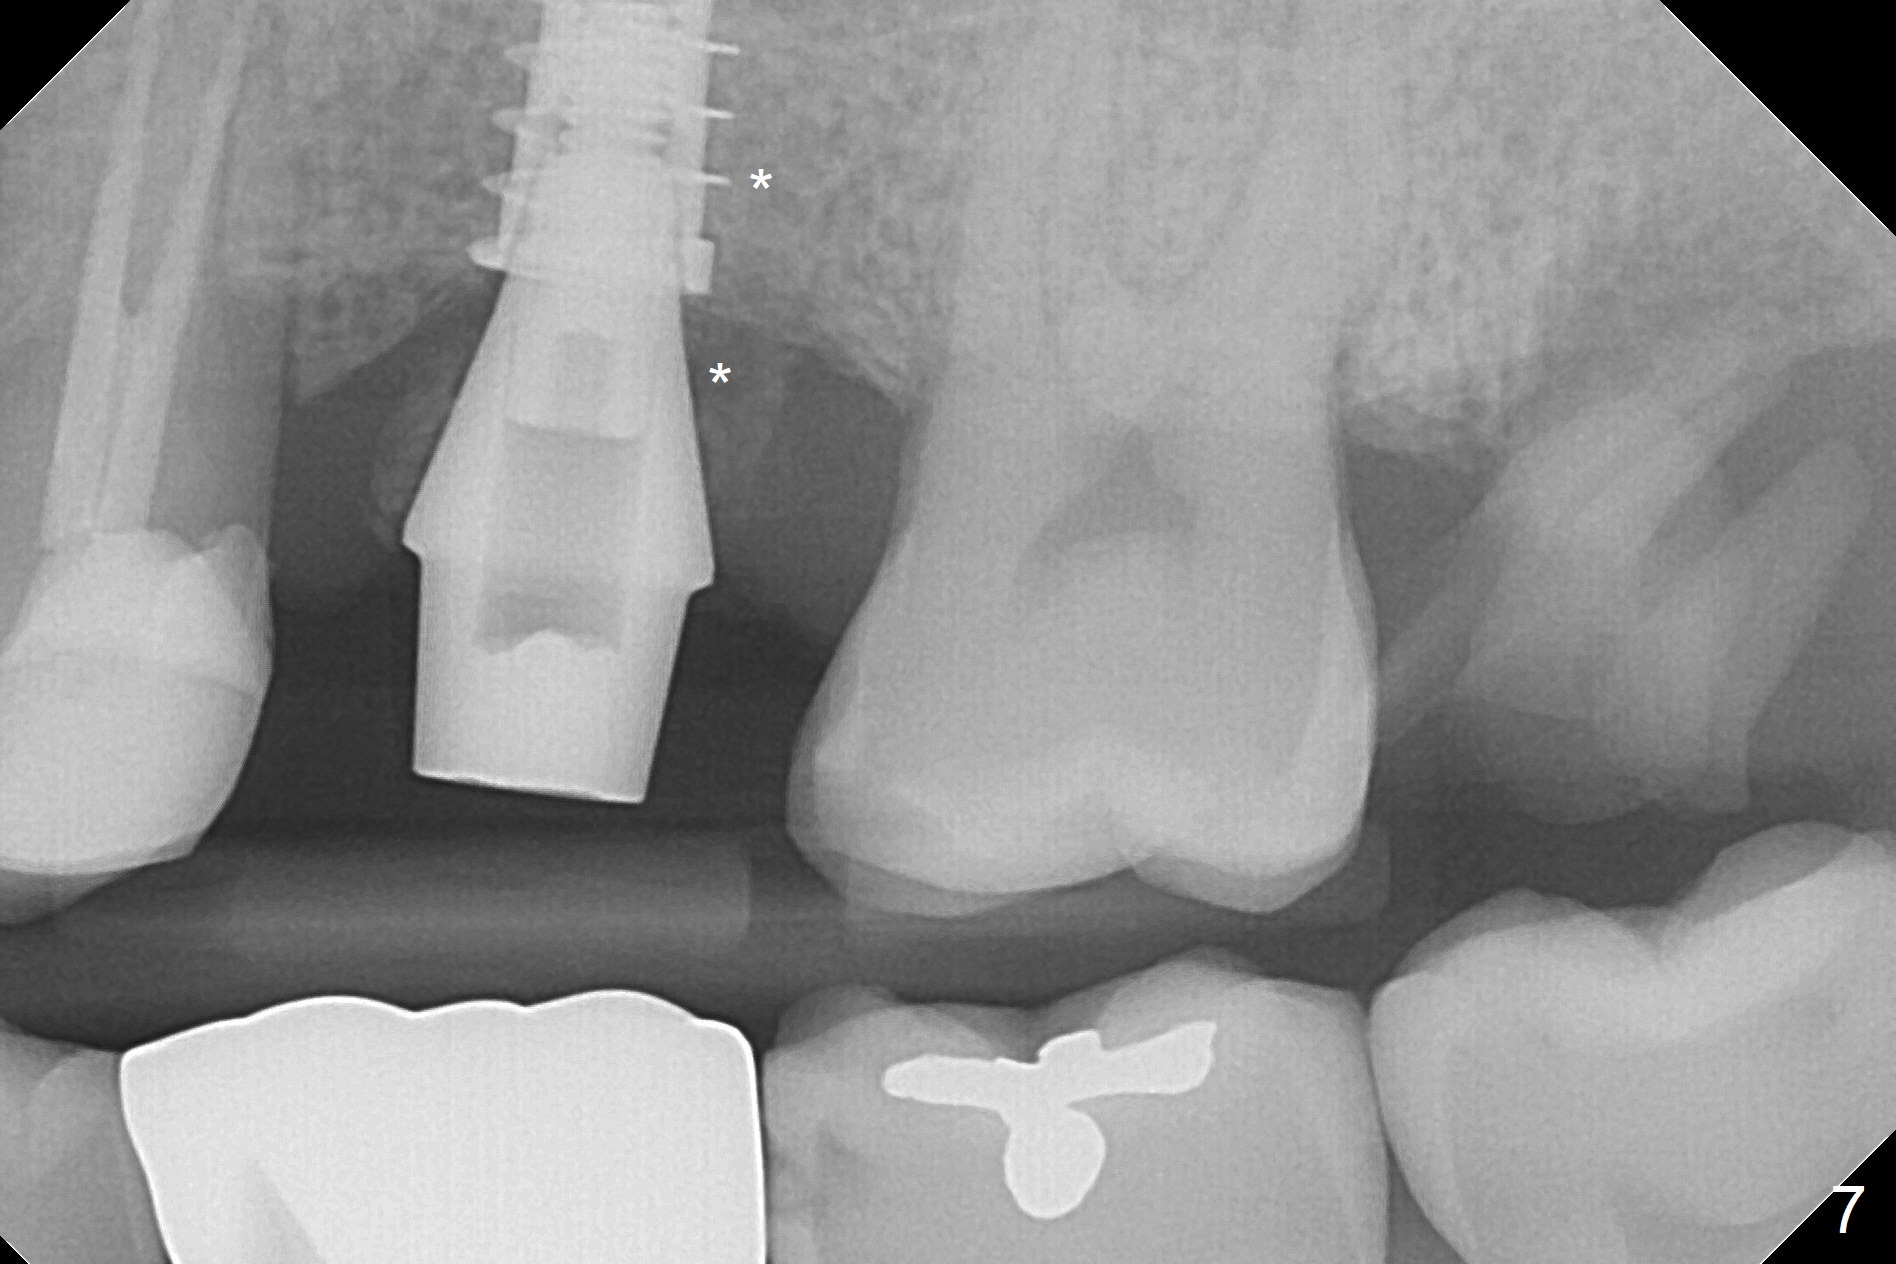

After extraction of the distobuccal residual root of the tooth #14 (Fig.1 arrow), the gingiva around the socket does not look like the keratinized one (Fig.2 *). An osteotomy through the distobuccal socket would seem too buccal for immediate implant. The palatal gingiva feels too tough to be stretched. An incision is made (Fig.3 dashed line); with elevation, the thick flap is transferred buccally (curved arrow). An osteotomy is initiated in the palatal bone with 1.5 mm drill, followed by Magic Expanders until 4.3 mm for 11 mm (Fig.4,5). Following Magic Drill 3.8x13 mm, the sinus membrane is found to be perforated. The latter is repaired with Osteogen plug. A 4.5x9 mm IBS implant is placed with 50 Ncm (Fig.6). Osteogen plug and allograft (Fig.7 *) are inserted into the remaining distobuccal socket (reduced after bone expansion). When a 5.5x4(4) mm abutment is placed, the transferred flap appears to be adapted to the distobuccal defect (Fig.8 *). Later one suture is placed for fixation. After provisional insertion, periodontal dressing is applied. Nine days postop, the periodontal dressing dislodges. When the loose provisional is removed for recementation, the flap seem to have healed (Fig.9 *). The gingiva heals around the abutment 5 months postop (Fig.9); the distal socket appears to heal while the bone graft remains at the crest (Fig.11,12). When #30 develops buccal abscess, the patient masticates on the left, leading to loss of composite at #13 (Fig.14); in fact the abutment at #14 is incompletely seated.